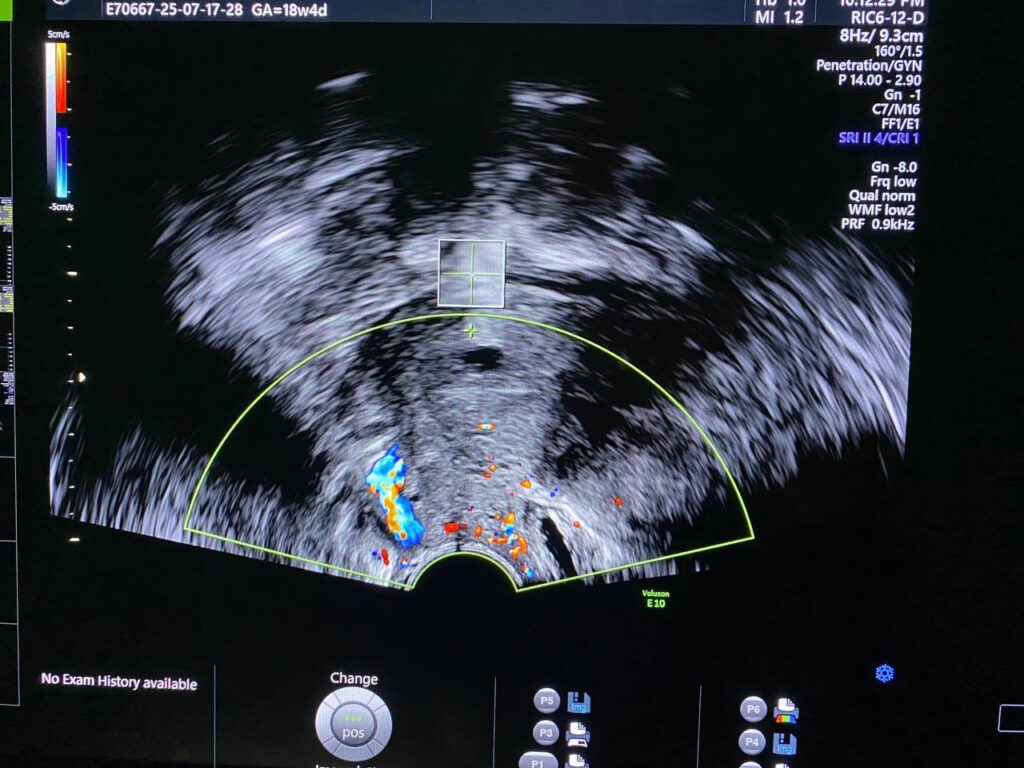

Normal size, A/V uterus, endometrial lining thickness 9.5mm, the myometrial layer is heterogenous in texture, with presence of vascular pedunculated mass with in the cervical canal and vaginal canal arise from internal os level (anterior wall) its size >60x10mm , pedunculated submucosal fibroid ?